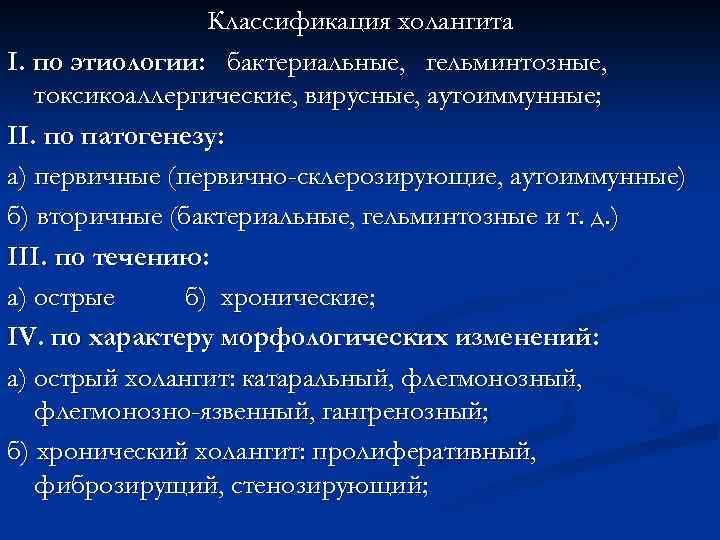

Классификация холангита I. по этиологии: бактериальные, гельминтозные, токсикоаллергические, вирусные, аутоиммунные; II. по патогенезу: а) первичные (первично-склерозирующие, аутоиммунные) б) вторичные (бактериальные, гельминтозные и т. д. ) III. по течению: а) острые б) хронические; IV. по характеру морфологических изменений: а) острый холангит: катаральный, флегмонозно-язвенный, гангренозный; б) хронический холангит: пролиферативный, фиброзирущий, стенозирующий;

Классификация холангита I. по этиологии: бактериальные, гельминтозные, токсикоаллергические, вирусные, аутоиммунные; II. по патогенезу: а) первичные (первично-склерозирующие, аутоиммунные) б) вторичные (бактериальные, гельминтозные и т. д. ) III. по течению: а) острые б) хронические; IV. по характеру морфологических изменений: а) острый холангит: катаральный, флегмонозно-язвенный, гангренозный; б) хронический холангит: пролиферативный, фиброзирущий, стенозирующий;

V. по степени распространения воспалительного процесса в желчных путях: а) сегментарный (вне- и внутрипеченочный), б) распространенный в) тотальный; VI. по характеру имеющихся осложнений: а) холангиогеннные абсцессы печени б) септические осложнения в) некроз и перфорация гепатикохоледоха; г) поражение паренхимы печени в виде перихолангиолита, фиброза портальных трактов с формированием вторичного билиарного цирроза печени; д) острая печеночная недостаточность.

V. по степени распространения воспалительного процесса в желчных путях: а) сегментарный (вне- и внутрипеченочный), б) распространенный в) тотальный; VI. по характеру имеющихся осложнений: а) холангиогеннные абсцессы печени б) септические осложнения в) некроз и перфорация гепатикохоледоха; г) поражение паренхимы печени в виде перихолангиолита, фиброза портальных трактов с формированием вторичного билиарного цирроза печени; д) острая печеночная недостаточность.